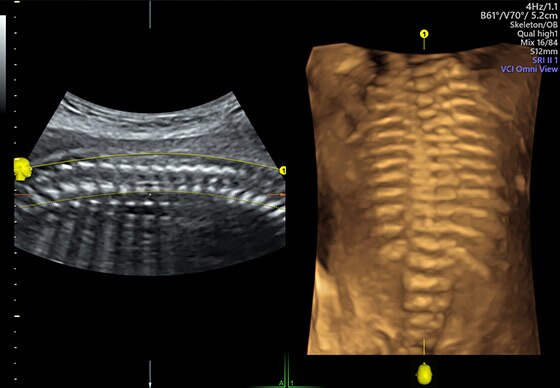

- 3D/4D Activation:

- Режим 3D.

- Режим 4D Realtime.

- SonoRenderlive – автоматическое определение границ конечностей и лица плода и получение объемного изображения в 3D/4D

- Advanced 3D/4D - расширенный программный пакет 3D/4D:

- Опция 3D/4D Activation (режим 3D/4D, SonoRenderlive – автоматическое определение границ конечностей и лица плода)

- Томографический ультразвук (TUI)

- Advanced VCI w/ Omniview - расширенный программный пакет объемного контрастного изображения (VCI) для объемных датчиков:

- Проведение любой произвольной плоскости в 3D/4D (OmniView)

- Объемное контрастирование любой произвольной плоскости (OmniView+VCI)

- Регулировка толщины и формы коронарного среза в 3D/4D (получение коронарной плоскости в 3D/4D, например, для оценки мозолистого тела - автоматическая функция "Corpus Callosum")